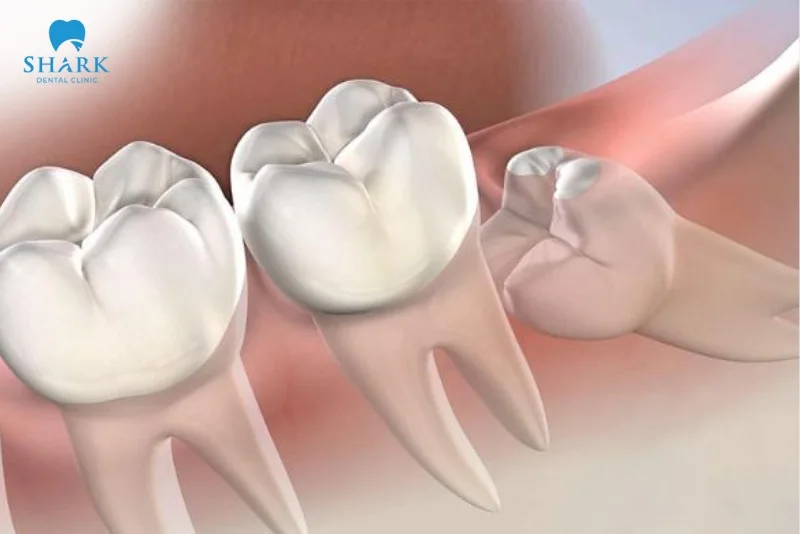

- Răng khôn mọc ngang hoặc mọc ngầm: Răng bị kẹt trong xương hàm, không thể trồi lên bình thường, thường gây đau kéo dài, sưng viêm và dễ hình thành ổ nhiễm trùng.